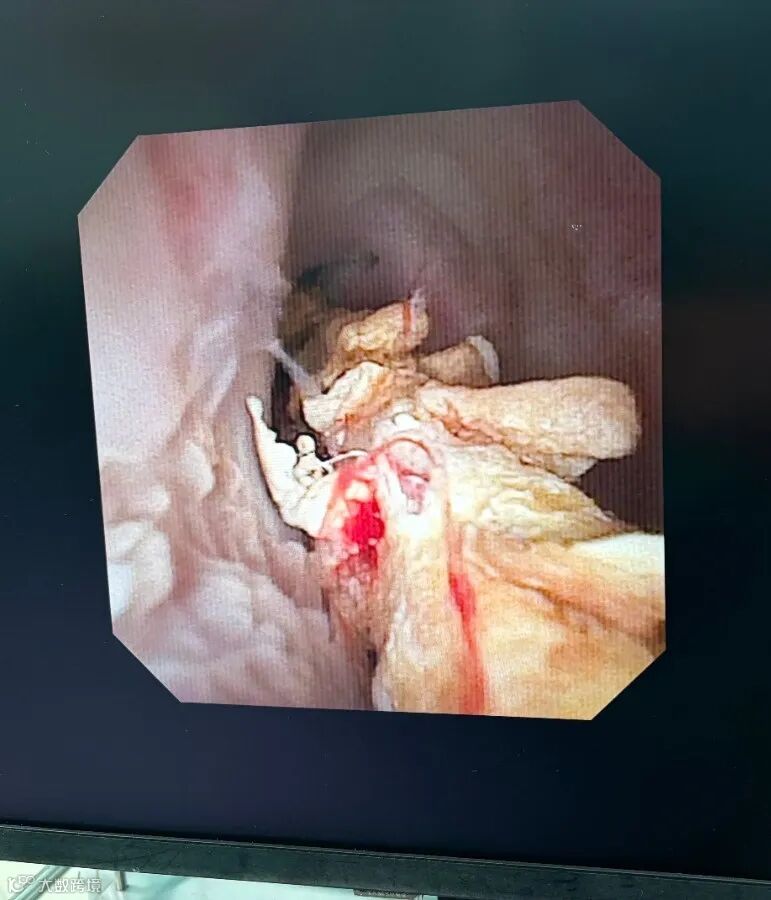

“切开并取出前端那两个像笔帽头一样的东西后,后面的情况更麻烦。”医生介绍,那是几段类似圆珠笔芯的异物,最长的一段约4厘米,短的有2厘米,其表面有类似“火腿肠花刀”的众多划痕。

正是这些划痕,为结石生长提供了绝佳的附着点,经年累月,异物表面完全被结石包裹、覆盖,形成了一株坚硬的“结石树”。这颗“树”在尿道内一路向下延伸,穿过尿道的生理弯曲,深度已接近直肠,最近处“可能只隔着一层膜”,操作稍有不慎就可能造成穿孔。

不仅如此,在取出笔芯状异物后,医生在附近又发现了数根竹签状异物。整个尿道因长期异物存留和炎症,已出现多处狭窄,进一步增加了手术难度。

手术团队面临着多重挑战:在狭窄且已受损的尿道内操作;需用激光精准击碎包裹异物的坚硬结石,又不能损伤本就薄弱的尿道壁,尤其要避免穿透至直肠;最后还需将异物分节安全钳出。整个过程需要医生在极为局限的空间内进行稳定而精细的操作。“操作时需要长时间保持手的稳定,对体力和专注力都是极大考验。”主刀医生陆顶进表示。最终,历经三小时,所有异物被成功“拆除”。

手术取出的异物